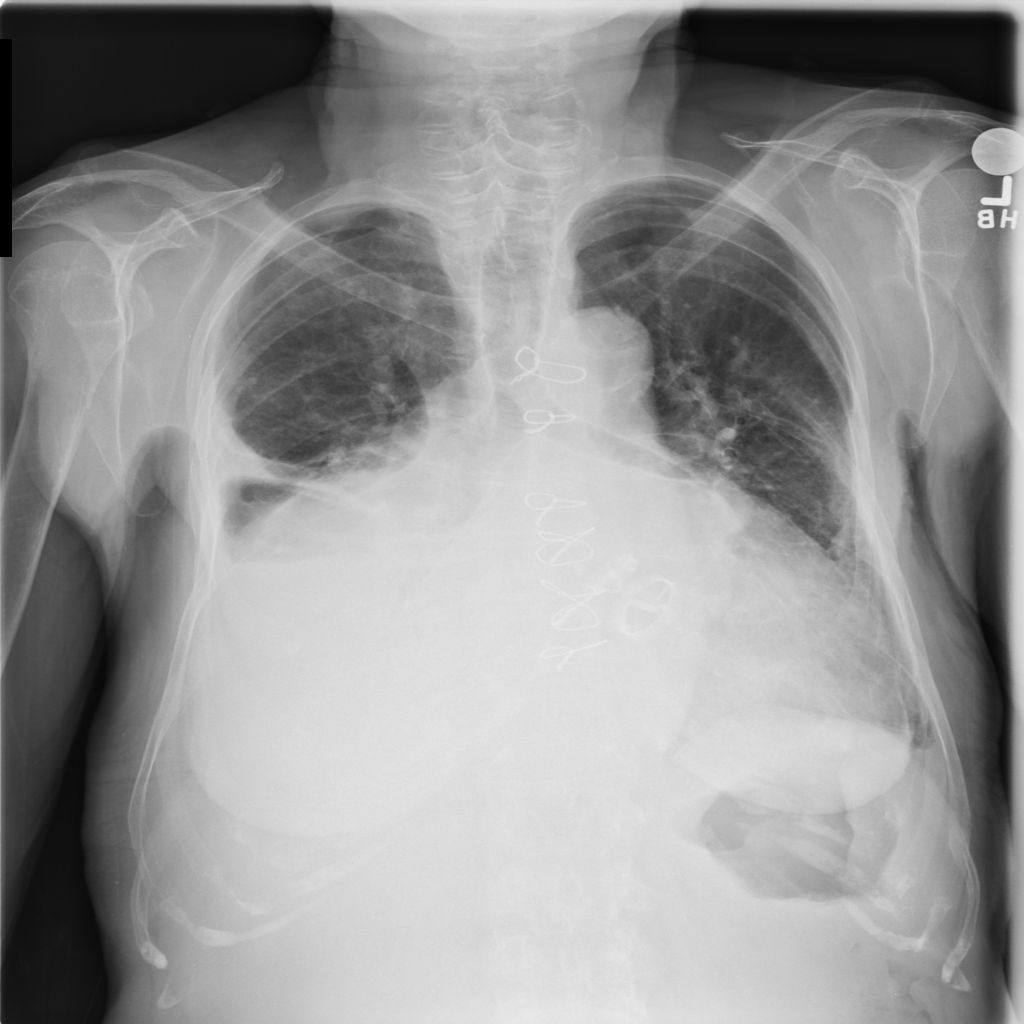

Pleural Effusion

Pleural effusion means extra fluid has collected around the lung in the pleural space. It can happen with heart problems, infection, inflammation, or other underlying conditions.

Showing up to 90 reference images for Effusion.

PAT-4639 · IMG-021Effusion

PAT-4639 · IMG-021

PA